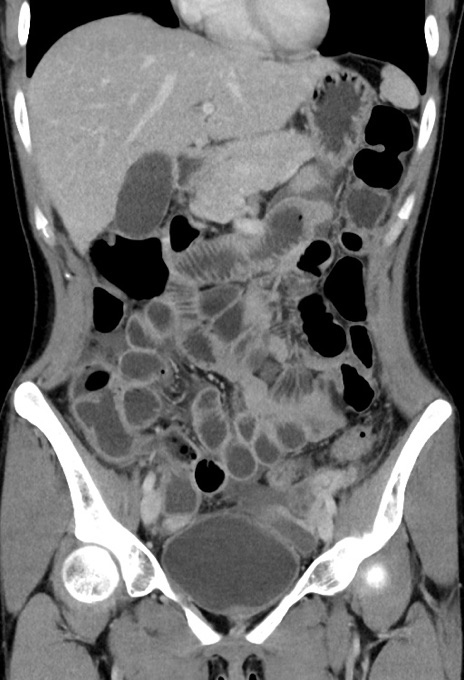

症例17(冠状断像)

【症例】20歳代女性

【主訴】嘔吐、下腹部痛

【現病歴】昨日夕食後に嘔吐し下腹部痛が出現。本日になっても嘔吐持続し改善しないため来院。

【身体所見】意識清明、BT 37.2℃、BP 108/67mmHg、腹部:平坦、やや硬、下腹部正中から右にかけて圧痛あり、反跳痛軽度あり、tapping pain(+)。

【データ】WBC 13600、CRP 14.94